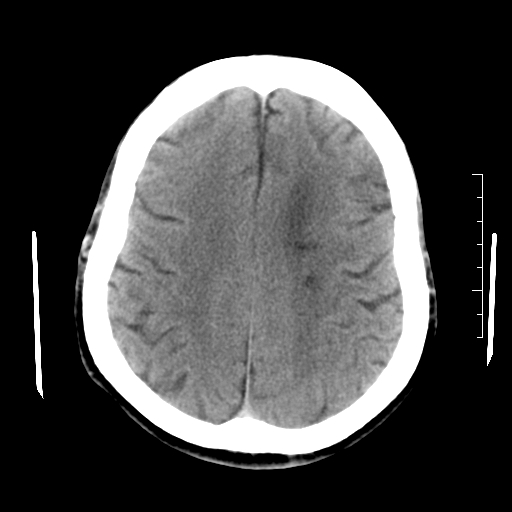

以下是引用随光逐影在2010-7-22 20:48:00的发言:[br]1)考虑左侧颞枕叶及左侧小脑脑梗塞。2)左侧半卵圆中心多发性腔隙性脑梗塞。[br]建议:必要时行mri检查。

以下是引用linyiming在2010-7-23 1:17:00的发言:[br])考虑左侧颞枕叶及左侧小脑脑梗塞。2)左侧半卵圆中心多发性腔隙性脑梗塞。[br]建议:必要时行mri检查。 [br]